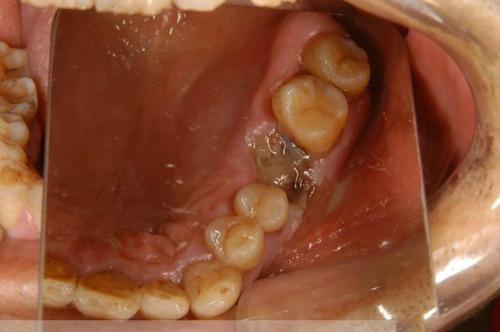

歯肉がんは、初期には目立たず、小さなしこりのようなもので、通常は放置されやすい。その後、少しずつ大きくなり、潰瘍化し、出血しやすくなる。このとき、歯肉炎か歯周炎か、歯磨きが悪いのだと思い、真面目に歯を磨いたり、消炎・止血効果のある歯磨き粉を買ったりする人がいる。

これらも、抗炎症薬が含まれている助けにはなりませんが、潰瘍の腫れが拡大し続け、さらには歯槽骨に進行し、歯槽骨が吸収され、歯が緩んで脱落しているように見え、発育し続けることも顔面肥大、咀嚼困難、口を開けるなど、局所的な痛み、口臭などを引き起こす可能性があります。

歯肉がんの症状は、歯肉にしこりができ、歯肉から頻繁に出血する。しこりは急速に成長し、後方に移動して歯槽骨や顎骨に浸潤し、骨を破壊して歯がゆるみ、痛みを引き起こす。臼歯の後方部や咽頭にも広がり、口が開きにくくなり、咀嚼や食事に影響を及ぼし、栄養不足になる。腫瘍細胞はリンパ系に入り、頸部のリンパ節に転移し、局所の腫れや痛みを引き起こし、進行すると肺や肝臓などの臓器に転移する。

1.初期の歯肉癌は、歯肉の縁に潰瘍ができ、痛みを伴う症状があり、歯周炎や歯肉炎と間違われることが多く、区別がつきにくいので、注意して観察し、警戒を高める必要があります。

2.中期の臨床症状は、歯茎の出血、骨浸潤の破壊、歯の緩みや痛みなどがあります。この時期には、症状がより顕著になる傾向があるため、必要に応じてX線撮影などの歯科的画像診断を行い、さらに病理学的画像診断を行って診断を明確にする必要があります。

(1) ガムの塊:主な症状は、歯肉に潰瘍や乳頭ができることである。

(2) 歯茎の痛み:主に腫瘍組織の隣接組織への浸潤が骨を破壊し、痛みを引き起こす。

(3) 歯が緩んでいる:これは主に、腫瘍細胞が骨を破壊し、歯が緩むことが原因である。特に、抜歯を伴う一般的な歯科疾患として治療した場合、傷が治らず、さらに歯が緩む可能性がある。

歯肉癌の症状は主に歯肉の腫れとして現れ、時間の経過とともに腫れは徐々に大きくなり、色が変わり、ひび割れ、破折、出血などが起こります。腫瘍の進行に伴い、ひどい場合には歯が抜けたり、顎が折れたりすることも現れ、腫瘍がリンパ節に転移した場合には頸部の腫大も現れます。

歯肉がんは、初期段階ではゆっくりと成長し、通常は潰瘍の形成や外側に膨らんだ増殖で現れ、歯肉の痛みや歯が抜けるなどの症状を引き起こします。

歯茎のしこりや潰瘍歯肉にしこりができたり、潰瘍ができたりすることがある。

歯ぐきの痛み、出血歯肉に痛みを感じたり、歯肉から出血しやすくなったりすることがよくあります。

乱杭歯がん病巣に対応する部分の歯が緩んだり、ずれたり、あるいは抜けたりすることがあります。抜歯した場合、傷が治らず、さらに歯が緩んだり浮き上がったりすることが見られます。